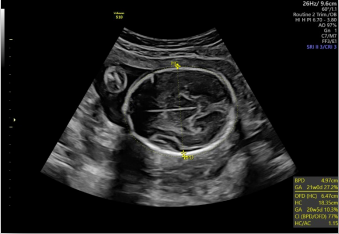

生長(zhǎng)指標(biāo)半自動(dòng)測(cè)量

在合適切面下,可自動(dòng)識(shí)別測(cè)量臨床所需的胎兒雙頂徑,頭圍,腹圍,股骨長(zhǎng)和肱骨長(zhǎng)度等多個(gè)參數(shù)。